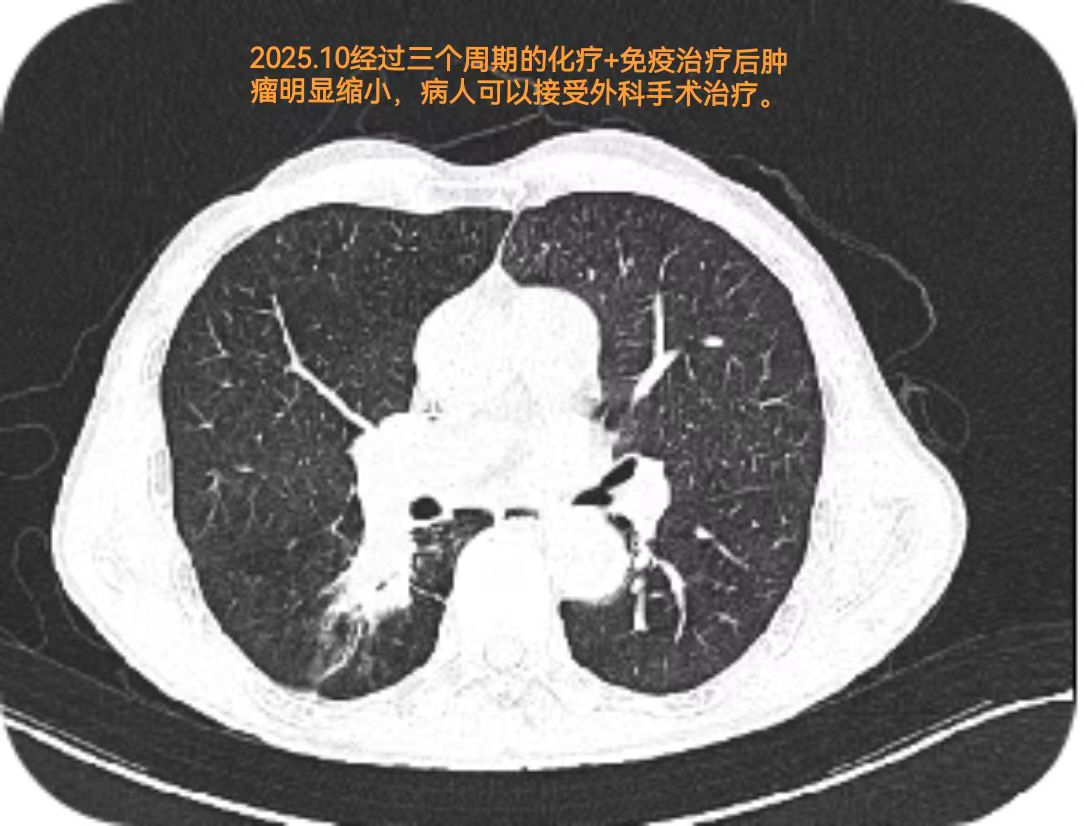

二、MDT会诊:量身定制转化治疗方案 面对吴伯的复杂病情,医院立即启动多学科诊疗(MDT)机制。肿瘤科、放疗中心、病理科、呼吸科及胸外科专家迅速集结,围绕患者年龄、身体基础条件、肿瘤病理特征等展开全面评估与讨论。 专家团队指出:“暂无法直接手术不代表没有治疗方向,转化治疗是当前局部晚期肺鳞癌的重要诊疗策略。”经过多轮严谨讨论,最终制定个性化方案:先予2周期“化疗联合免疫治疗”,通过药物控制肿瘤进展、缩小病灶,待病情改善后再评估手术可行性。 按照方案,吴伯完成2周期治疗后,咳嗽、胸闷等症状明显缓解,复查影像学提示肿瘤出现退缩迹象;专家团队随即调整方案,追加1周期强化治疗。3周期治疗结束后,再次MDT评估显示:肿瘤明显缩小,已达到手术切除条件。原本暂不具备手术条件的病灶,成功转化为可切除状态。 三、专家协作:手术切除病灶,守护肺功能 手术是控制病情的关键一步。为确保手术安全与效果,我院胸甲状腺乳腺血管外科主任于福田与科室医生陈圣旋联袂主刀,麻醉科团队全程保驾护航,为吴伯实施复杂肿瘤切除术。 手术中,专家团队凭借精湛的操作技术与默契的协作配合,精准分离病灶、清除肿瘤组织,同时最大限度保护正常肺功能。历时数小时,手术顺利完成:不仅完整切除病灶,还同步切除该侧上肺叶的肺大疱,为吴伯术后肺部功能恢复创造了有利条件。 术后病理结果进一步印证了诊疗方案的科学性:吴伯病理分期(pTNM)改善为T3N0Mx,提示肿瘤已无淋巴结转移,达到了临床预期的治疗效果。这一成果为延长吴伯的生存期、提升后续生活质量奠定了坚实基础。 四、“家门口”的医疗服务:守护百姓健康,助力康复希望 从“暂无法手术”到“成功切除病灶”,吴伯的诊疗过程,是我院医疗水平提升的缩影。近年来,医院坚守“以患者健康为中心”的理念,聚焦群众就医需求,通过引进专家、强化多学科协作、加强专科建设,提升了疑难病症诊疗能力。